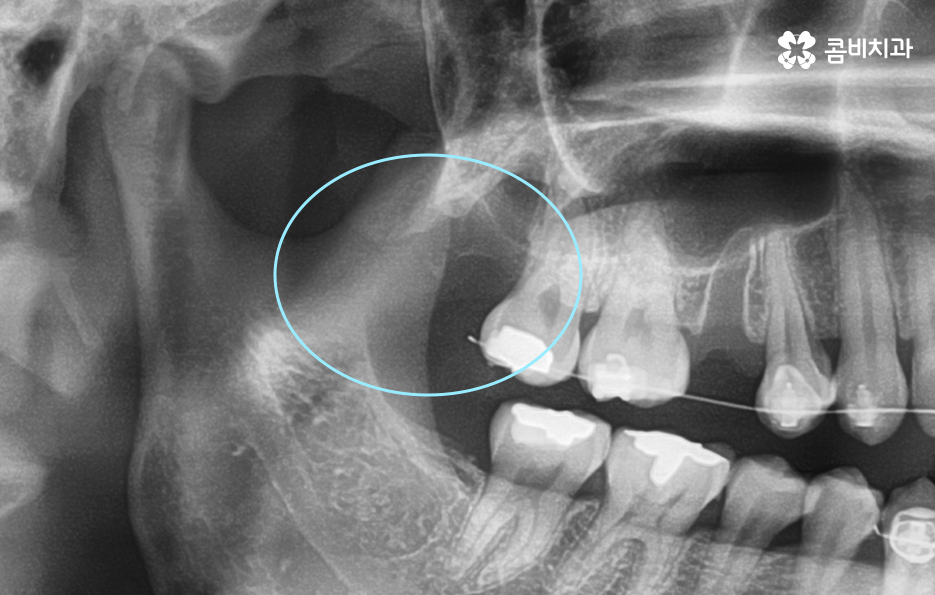

현대인들의 경우 사랑니가 4개 모두 나기 보다는 1~3개 씩 나는 경우도 많고 요즘 젊은 분들은 턱 뼈가 좁은 편인 분들이 많다보니 사랑니가 나올 공간이 부족하여 매복사랑니를 갖고 계신 경우도 많이 있어요

그리고 보편적으로는 윗니의 경우 중력에 의해 사랑니가 똑바로 나오는 경우가 좀더 많다면 아랫니의 경우 누워서 자라는 경우가 좀 더 많이 있는데요. 사랑니는 이처럼 나오는 위치나 방향의 개인차도 크고 정상적으로 똑바로 나온 경우에도 칫솔질이 잘 닿지 않거나 치석이 쌓이기 쉬운 위치이다 보니 결국 발치로 이어지는 경우가 많을 거예요

매복사랑니의 경우 당장 발치가 필요하지 않은 경우에도 주기적으로 치과 검진을 통해 사랑니의 상태를 체크할 필요가 있으며 특히 어금니 뿌리 쪽에 안좋은 영향을 주고 있거나 우려가 있다면 발치 계획을 세워야 할 거예요

일반적으로 상악보다는 하악이 하치조 신경과 턱뼈가 근접하기 때문에 좀더 세심한 발치를 해야하며 정상 맹출된 사랑니 보다는 완전 매복되어 있는 사랑니 발치가 고난도의 발치로 분류되고 있어요